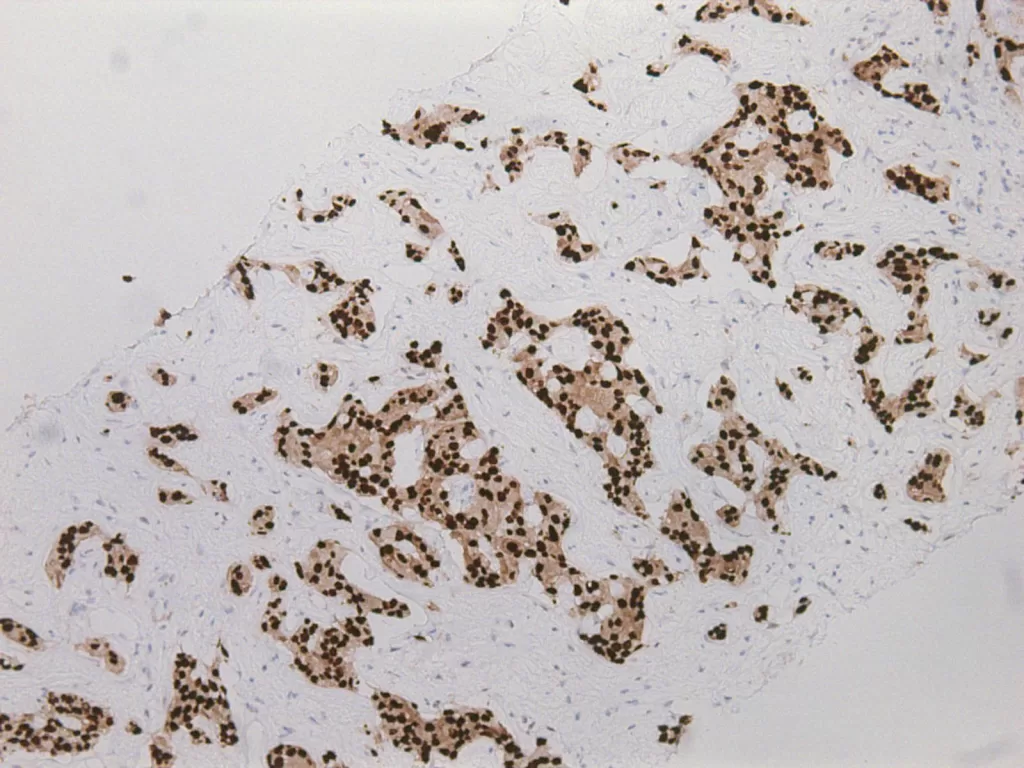

ER(雌激素受體):讓我們知道癌細胞是否依賴雌激素而活。若為陽性,可以用荷爾蒙治療像關掉電源般,讓它靜下來,不再被過度刺激。

當妳做完乳房攝影或超音波,那一小片被切下的組織會進入顯微鏡的世界。病理醫師在那裡看見平常看不見的部分,那些色彩、結構與節奏,試著從中解讀身體的語言。最後的病理報告不僅僅是診斷,更是傳達了妳的身體在說什麼、帶來了怎麼樣的希望。